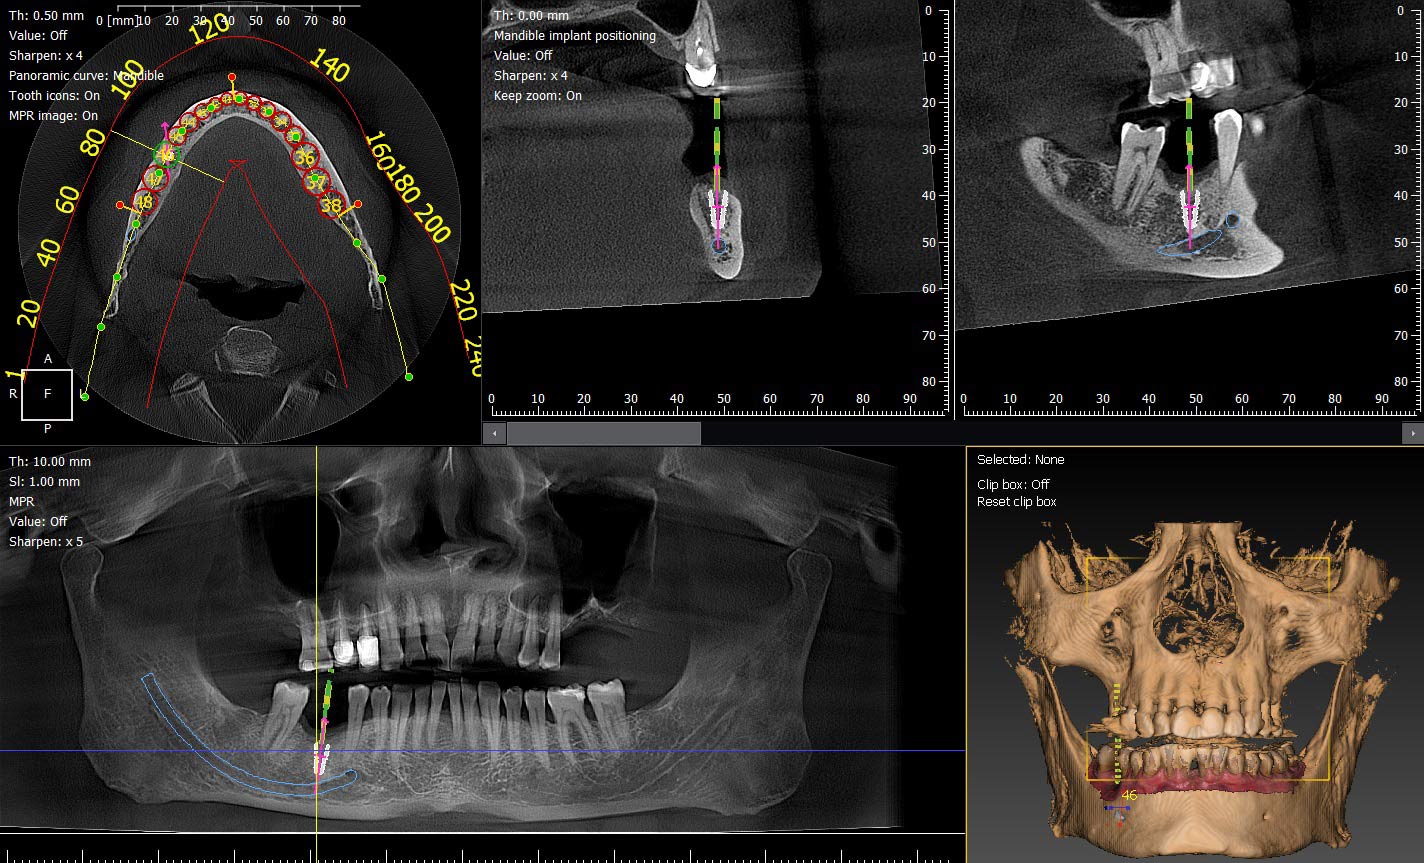

L’imagerie dentaire connaît une évolution majeure. Grâce à l’intégration de l’intelligence artificielle et de capteurs de nouvelle génération, le CBCT dentaire franchit un nouveau cap en matière de précision diagnostique, de réduction de dose et de qualité d’image. Ces innovations technologiques transforment profondément la pratique quotidienne des chirurgiens-dentistes et des spécialistes.

- Résolution ultra-fine jusqu’à 70 µm par voxel, idéale pour l’analyse endodontique, implantaire et parodontale

- Meilleure dynamique de contraste à faible dose, permettant d’obtenir des images plus lisibles tout en réduisant l’exposition aux rayons X

- Réduction significative du bruit d’image, améliorant le rapport signal/bruit (SNR) et la netteté globale

- Amélioration d’environ 30 % du flou de bord, lors de la conversion des rayons X en lumière au niveau du scintillateur